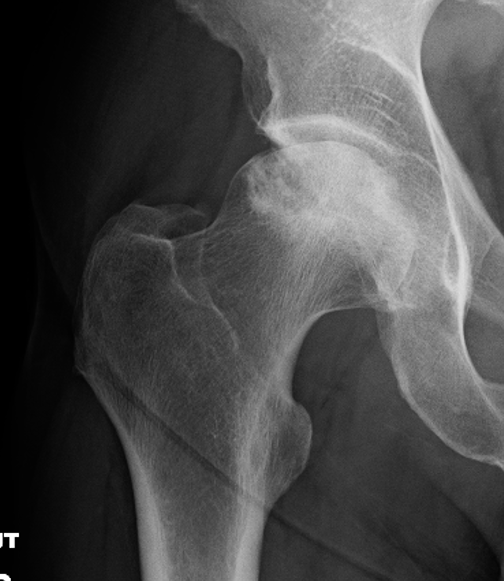

Xray

Stage III: collapse / flattening femoral head with preserved joint space